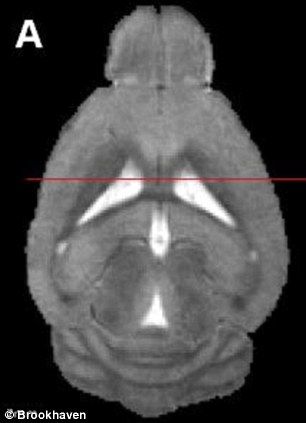

为植入假记忆,研究人员设计了老鼠大脑中控制回忆的细胞。为植入假记忆,研究人员设计了老鼠大脑中控制回忆的细胞。

新浪科技讯 北京时间7月29日消息,据国外媒体报道,把思想植入某人大脑是好莱坞恐怖片的情节。而研究人员在把科幻情节变成现实的实验中,已经成功地植入假记忆。美国麻省理工学院科学家已证实,可在现实生活中做到这一点,至少在老鼠身体上是这样。